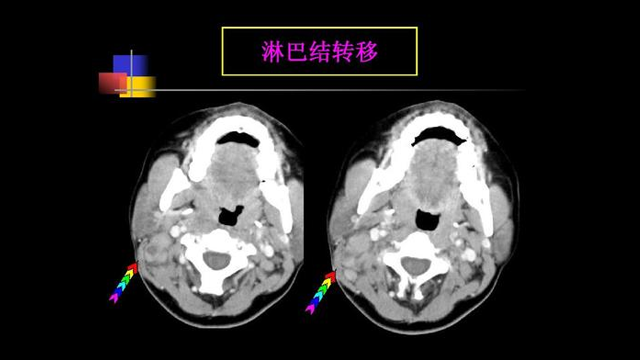

4.颈部淋巴结肿大

脖子一边大一边小,肿大的淋巴结无疼痛,质较硬,活动度差,逐渐迅速增大并且固定,多个肿大的淋巴结可互相融合成巨大肿块。